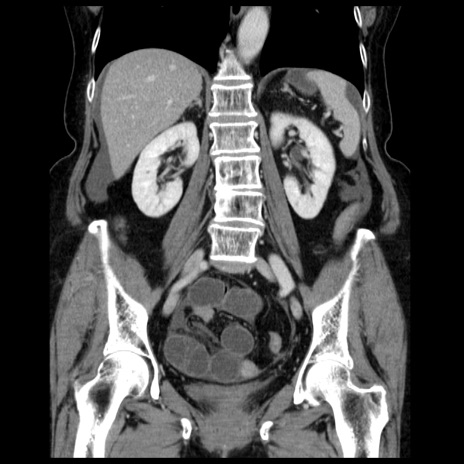

【症例】70歳代女性

【主訴】腹痛、嘔吐

【現病歴】15時間程前(昨晩)より腹痛あり。今朝になっても症状の改善なく、嘔吐あり。腹痛も増悪あり、救急外来受診。

【既往歴】子宮癌全摘術後

【身体所見】意識清明、BP 121/72mmHg、P 74bpm、SpO2 100%(RA)、腹部:平坦・軟、腸雑音ほぼ聴取せず。下腹部・心窩部・臍左上に圧痛あり。反跳痛なし。

【データ】WBC 10600、CRP 0.15